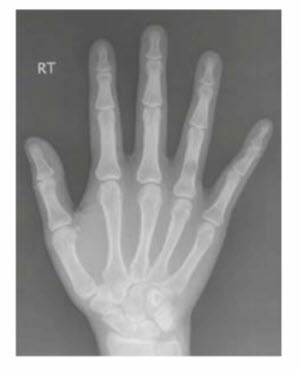

This is the most common primary benign bone tumor of the hand and wrist and is of cartilage origin. Up to 90% of all bone tumors in the hand and wrist are enchondromas, with 35 to 54% of all enchondromas occurring in the hand and wrist. They are often found incidentally on X-rays taken for other reasons (eg, hand trauma). They are usually solitary and favor the diaphysis of small tubular bones and are most common in the second and third decades of life. The most common location is in the proximal phalanges, followed by the metacarpals and then middle phalanges. Enchondroma has never been reported in the trapezoid. Presentation is usually asymptomatic, but pain may occur if there is a pathologic fracture or impending fracture. The etiology is believed to be from a fragment of cartilage from the central physis. Histology shows well-differentiated hyaline cartilage with lamellar bone and calcification. Two variants of enchondroma include Ollier disease (multiple enchondromatosis) and Maffucci syndrome (multiple enchondromatosis associated with multiple soft tissue hemangiomas). Malignant transformation is very rare in the solitary form, but there is a 25% incidence by age 40 in Ollier patients and a 100% life-time incidence in Maffucci patients. When malignant transformation does occur, it is almost uniformly a chondrosarcoma with pain and rapid growth. Diagnosis is usually made based on history, physical examination, and X-rays. There is a well-defined, multilobulated central lucency in the metaphysis or diaphysis that can expand causing cortical thinning or sometimes, thickening (Fig. below). Further imaging is seldom needed, but a CT would be the study of choice.

Enchondroma. X-ray of the phalanx demonstrates a welldefined central lucency. Surrounding cortex may thin or thicken. Thinning of the cortex contributes to risk of pathologic fracture.